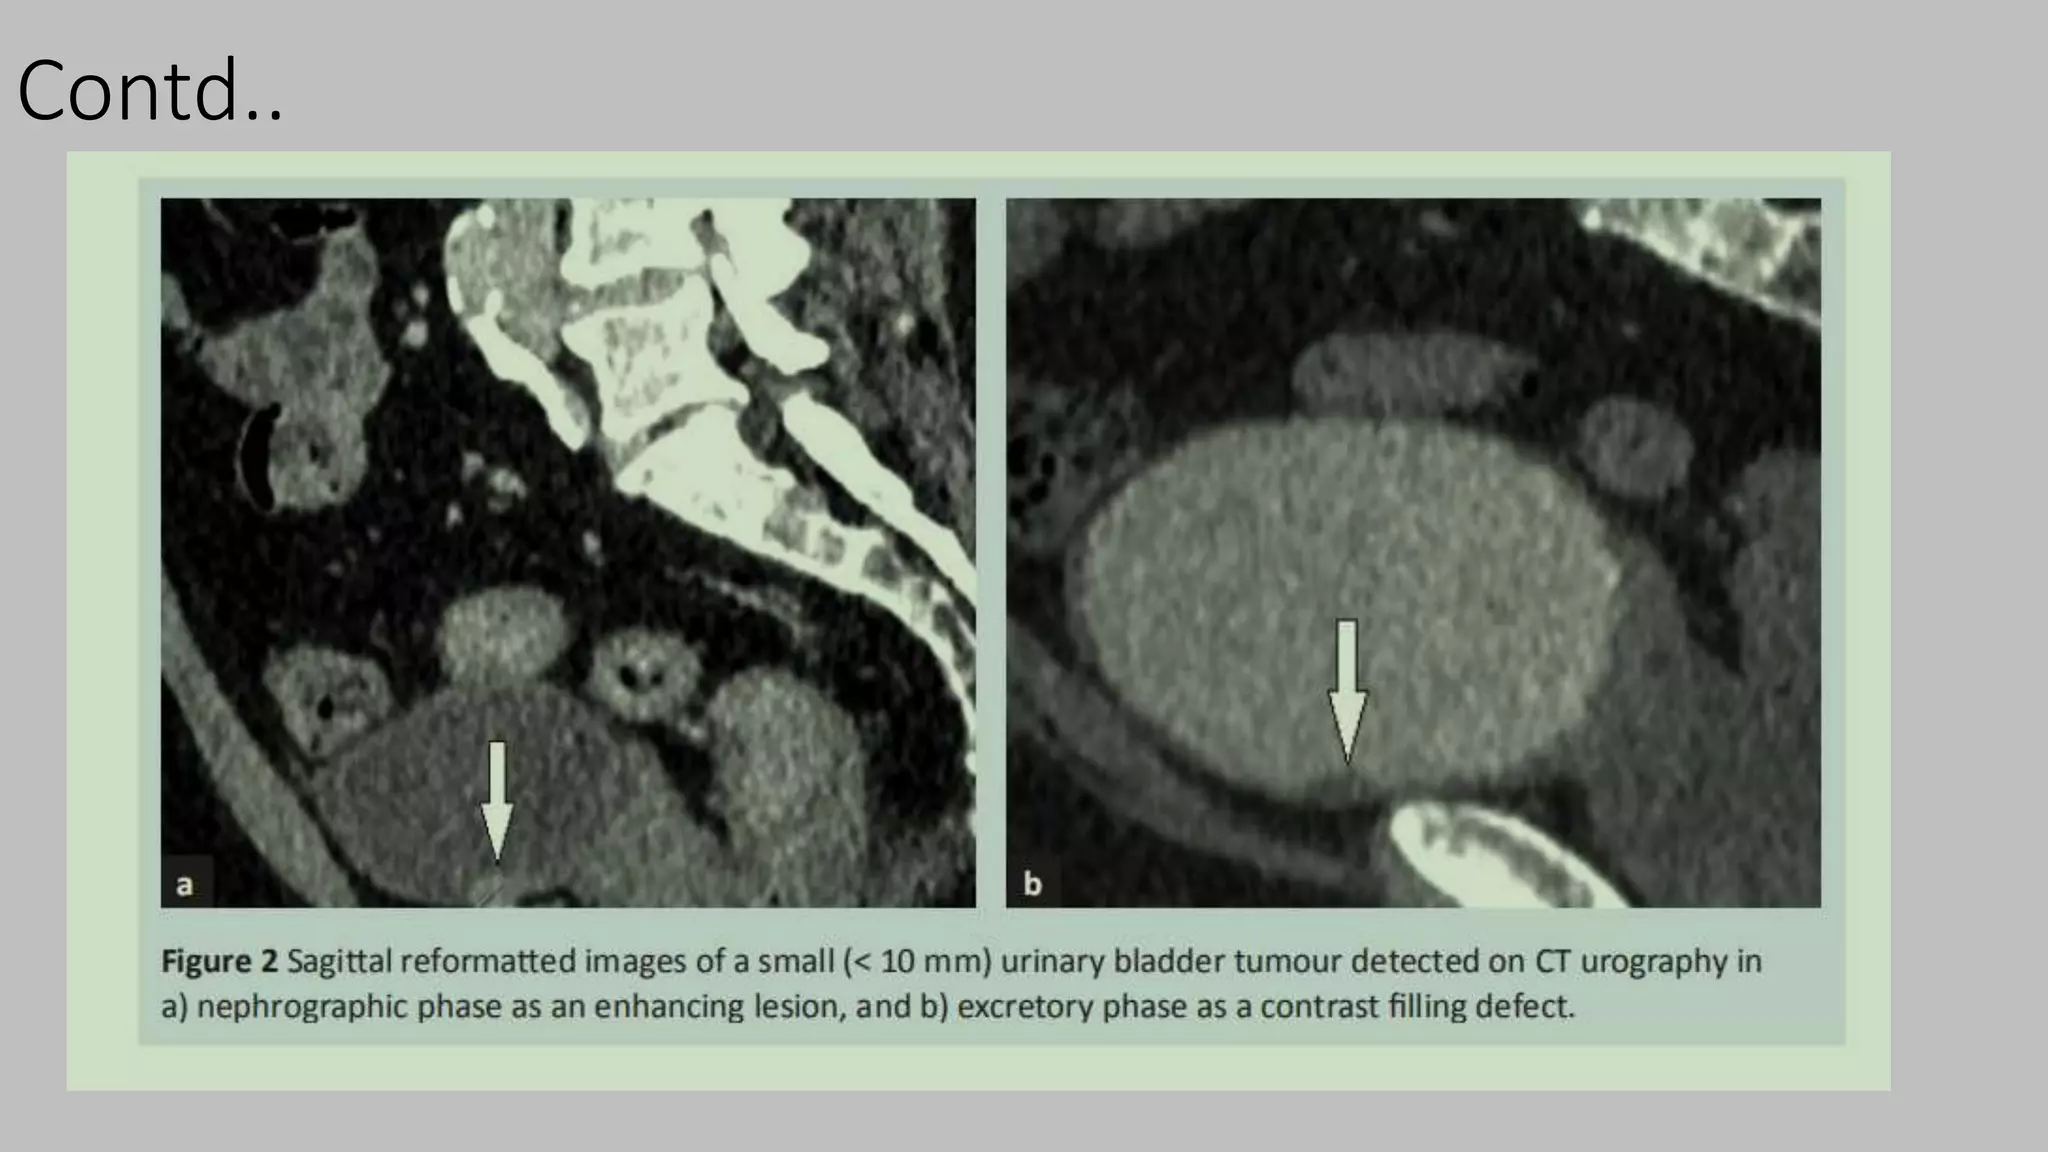

Excretory phase

• Begins approx 5-8 min after the start of contrast injection.

• The contrast excretes into the collecting system decreasing the attenuation of the

nephrogram

• helpful to better delineate the relationship of a centrally located mass with the

collecting system.

• also useful for evaluating urothelial masses.